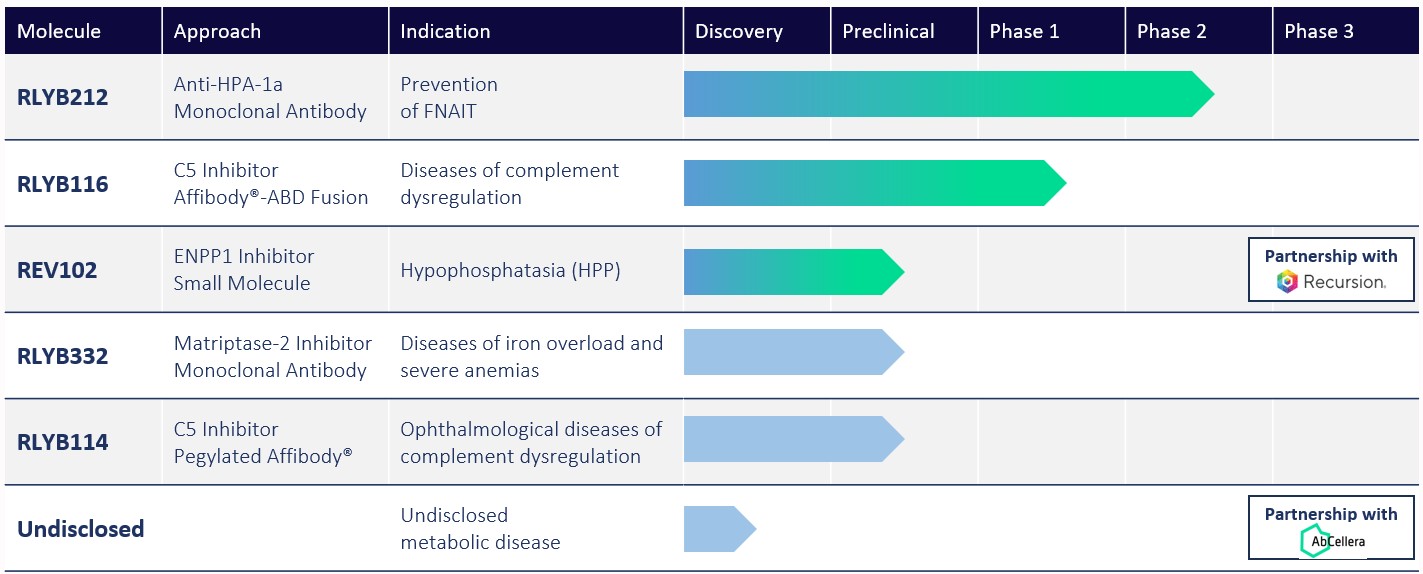

Our pipeline is illustrated in the chart below:

FNAIT: Fetal and neonatal alloimmune thrombocytopenia; HPA-1a: Human platelet antigen-1a; C5: Complement component 5; ABD: Albumin-binding domain; ENPP1: Ectonucleotide pyrophosphatase/phosphodiesterase 1